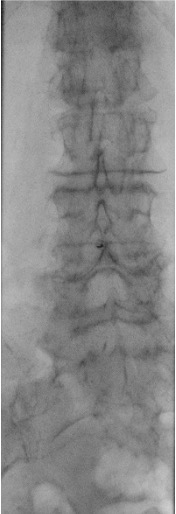

Place patient prone or prone oblique on the fluoroscopy table. Position a pillow under the abdomen to reverse lumbar lordosis and widen the interlaminar spaces. Identify the target interspace (L2–L3 or L3–L4) on fluoroscopy. For oblique positioning, the top leg is bent with arms by the side. Mark the skin entry point under fluoroscopic guidance.

Fluoroscopic approach views

AP fluoroscopic view showing midline approach for lumbar puncture Prone oblique fluoroscopic view showing paramedian approach for lumbar puncture Second prone oblique view showing needle trajectory for lumbar puncture